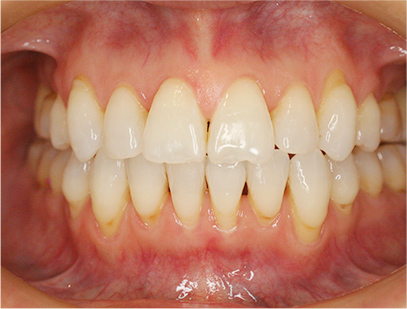

前歯にデコボコがあり、前歯が咬み合っていない症例

上下の前歯が咬んでいない事、上の前歯にデコボコがある事を主訴として来院されました。

通常通りの検査を行い「前歯部にデコボコを伴う開咬」と診断されました。

上顎は左右4番目の歯を抜歯して、下顎は横に拡大してスペースを利用して前歯を綺麗に並べ、そして前歯部にゴムを使用して咬み合わせを改善することにしました。

上下共に表側の白い矯正装置(セラミック)、マウスピース矯正

治療前の写真を比べると上下の前歯は綺麗に並び、歯が出ていたことも改善され、 上下の歯はしっかり咬み合っています。 治療期間は、重度の開咬であったために3年弱を必要としました。

• 歯並びが綺麗になり、上下の歯が咬み合った事。

• 上の前歯が出ていたことが改善された事。